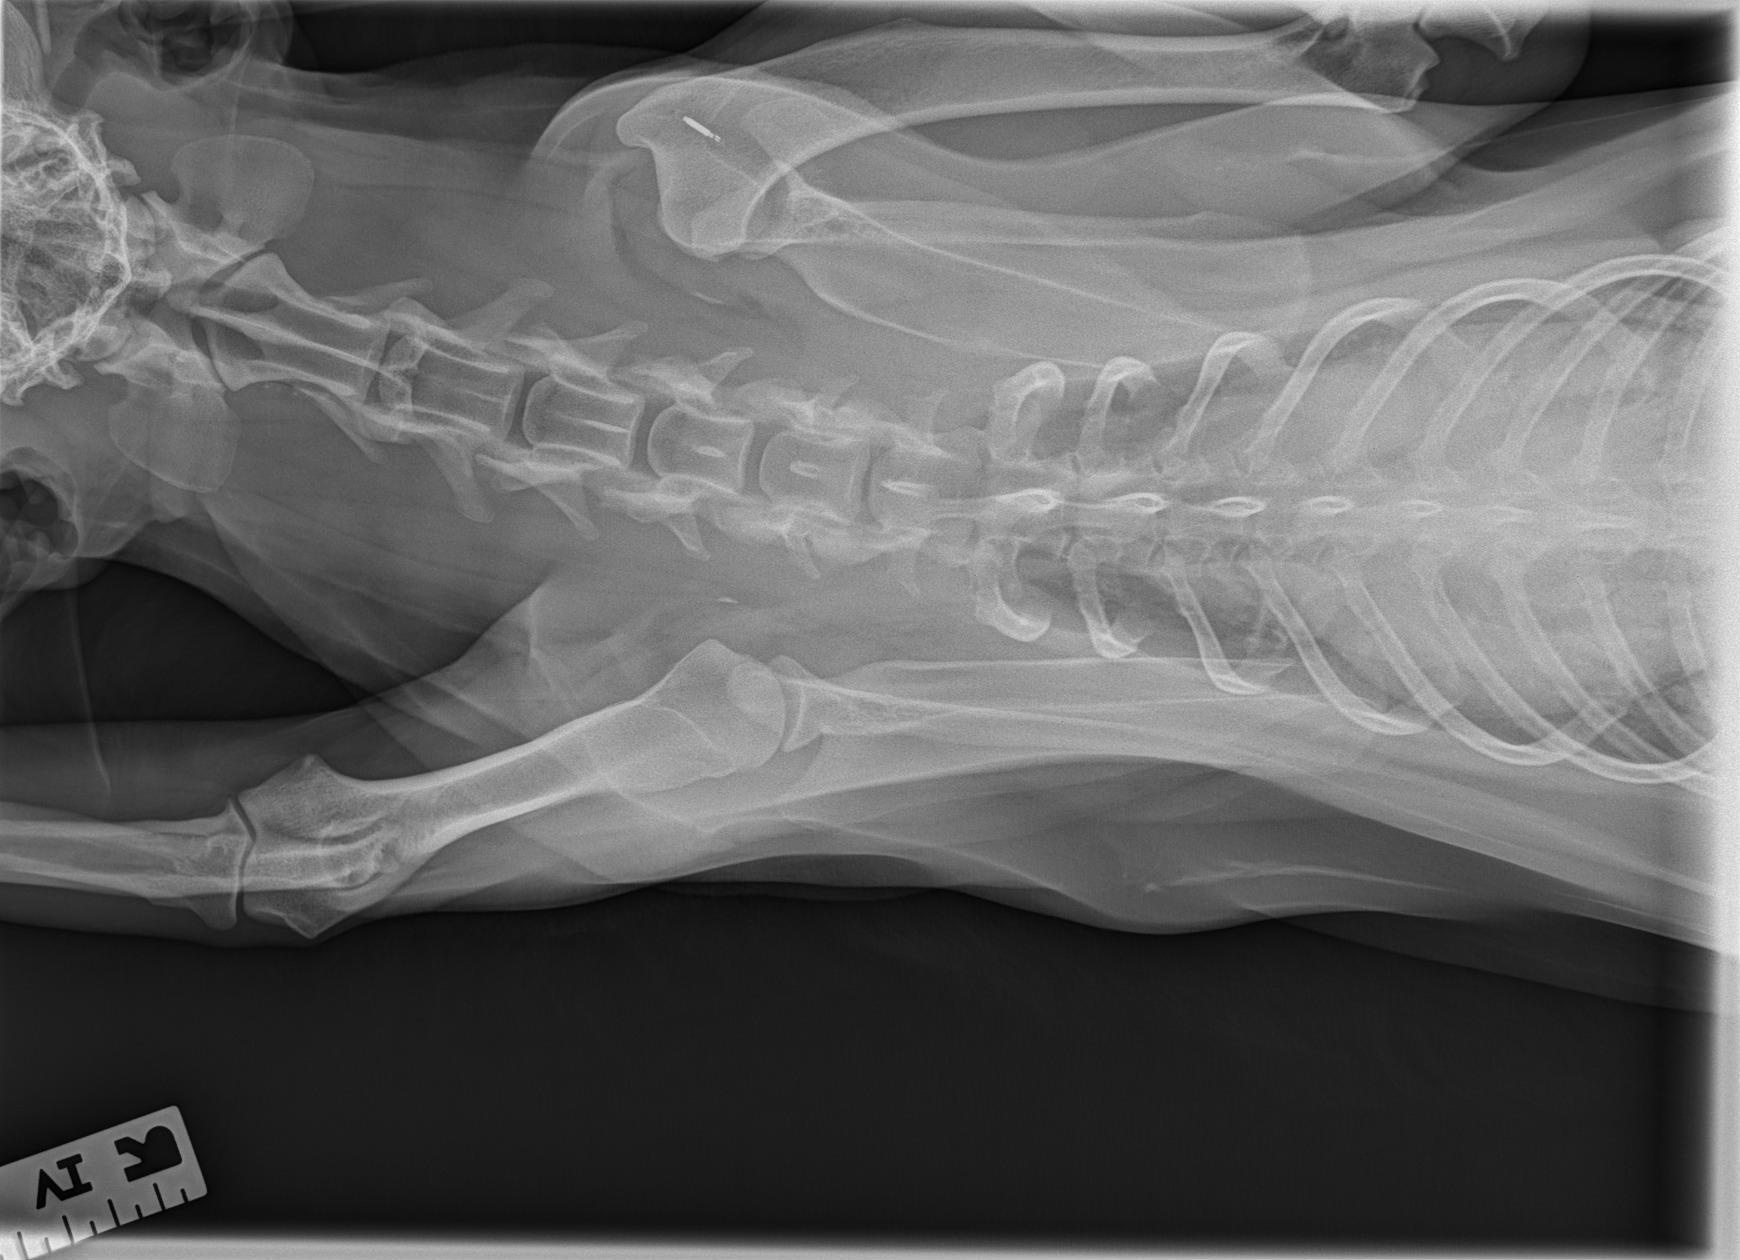

Des radiographies du thorax et du membre thoracique droit ont été réalisées à l’admission (vues latérales et dorso-ventrale).

Les clichés montrent :

- Une luxation latérale évidente de la tête humérale par rapport à la cavité glénoïde.

- Un déplacement de la tête humérale vers l’extérieur, sans fracture humérale ou scapulaire associée.

- Des contours osseux nets, compatibles avec une luxation évoluant depuis plusieurs jours.

- L’absence de lésion thoracique significative.

Ces images confirment la luxation chronique non réductible, orientant vers une stabilisation chirurgicale.